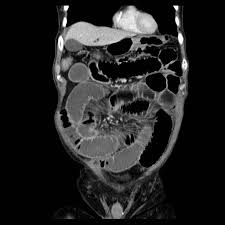

valvulae conniventes